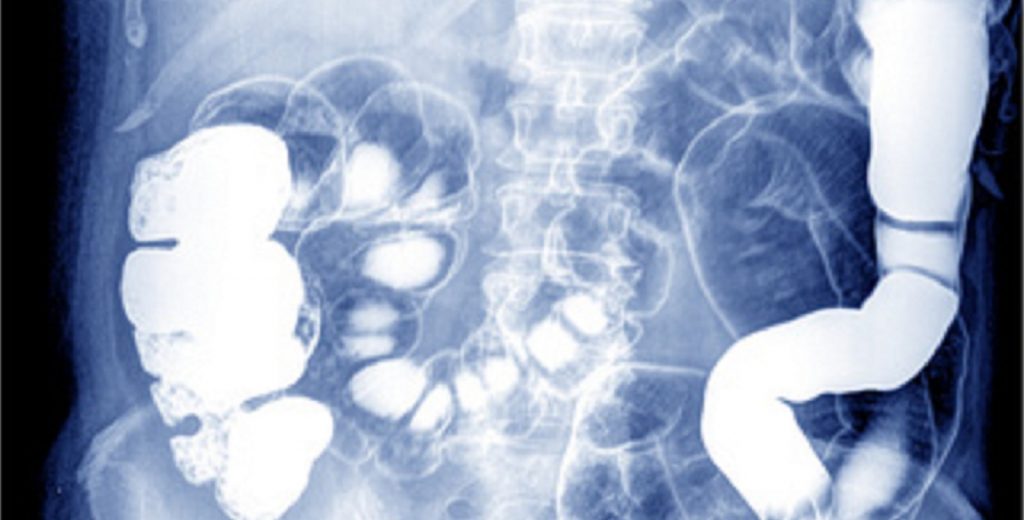

Die Leber ist ein wichtiges Organ im menschlichen Körper, welches sich im rechten Oberbauch befindet.

Die Leber ist an vielen Stoffwechselmechanismen beteiligt und wiegt zwischen 1500 und 2000 Gramm. Desweiteren besitzt die Leber eine Filterfunktion, die es ermöglicht, Giftstoffe, Medikamente oder Stoffwechselendprodukte abzubauen und auszuscheiden.

Alle Nahrungsbestandteile, die wir über den Darm aufnehmen, werden über die Pfortader (eine Arterie), zur Leber hin transportiert. Erst nachdem diese Stoffe einmal durch die Leber gelaufen sind, gelangen sie in den Blutkreislauf.